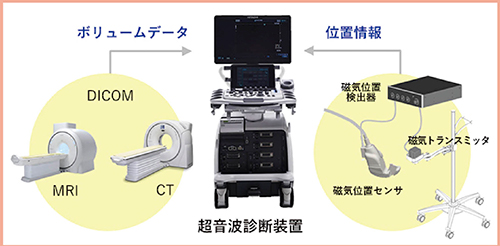

超音波フュージョン技術であるRVSは,磁気位置センサを用いて超音波画像と超音波プローブの走査面に一致したMRI/CT画像を同一モニタ上でリアルタイムに表示できる技術であり,日立が世界で初めて開発に成功した(図1)。

図1 Real-time Virtual Sonography (RVS)

(日立製作所ホームページより引用)